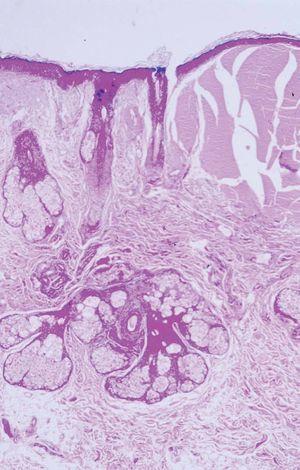

Fig. 3.--Acumulación de material eosinofílico, fisurado, bien delimitado, en dermis papilar. Epidermis atrófica con leve hiperqueratosis ortoqueratósica. (Hematoxilina-eosina, x100.)